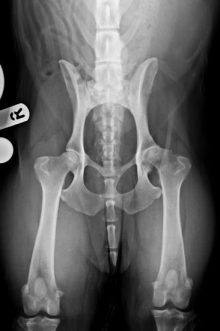

Gus is doing well following bilateral hip replacements

It was great to see Gus back in the clinical last week for his x-rays 6 weeks after the ...